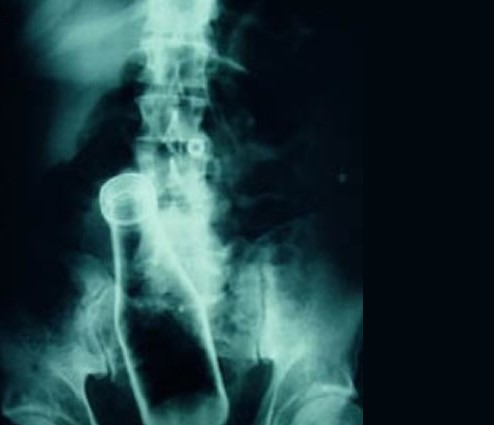

- SE APRECIA AL EXAMEN RADIOGRAFICO PRESENCIA DE CUERPO EXTRAÑO (BOTELLA VIDRIO) EN REGION RECTAL Y COLON SIGMOIDES.